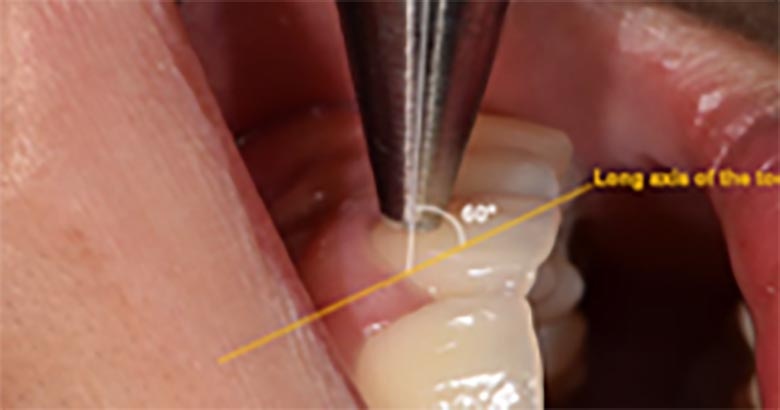

Все процедуры выполняли опытные преподаватели и резиденты в клинике. Перед проведением измерений каждый испытуемый отдыхал 10 минут в полусупинированном положении. Систолическое и диастолическое КД измерялось и регистрировалось с помощью цифрового сфигмоманометра (Angelus; KTMED, Сеул, Южная Корея). После был изучен КП каждого отдельного зуба с помощью прибора ультразвуковой допплерографии (MM-D-K, ЗАО «Минимакс», Санкт-Петербург, Россия) (рис.1). К компьютеру подключен ПВ-датчик 20 МГц с диаметром 1,5 мм. После сушки поверхности зуба перед измерением наносилось небольшое количество контактного геля для ультрасонографии (Pro-gel II, Dayo Medical, Сеул, Южная Корея). Датчик располагался на губной поверхности зуба под углом приблизительно 60° относительно продольной оси зуба. Эксперт искал сигнал, прослушивая пульсирующие звуки. Датчик помещали на место с самым четким звуком и удерживали в течение приблизительно 10 с, чтобы можно было записать стабильный и последовательный сигнал. После измерения записывались допплеровские спектры и рассчитывались индексы светового потока с использованием программы Minimax Doppler 1.71 («Минимакс», Санкт-Петербург, Россия) (рис.2).

РИСУНОК 1. 20 МГц датчик устройства ультразвуковой допплерографии (ЗАО «Минимакс», Санкт-Петербург, Россия). (A) Наконечник датчика. (B) Датчик удерживается в руке. (C) Позиционирование датчика на центральном резце.

Тип зуба не оказывал существенного влияния на СКП, что соответствовало предыдущему исследованию, в котором была проанализирована средняя СКП у 359 передних зубов верхней челюсти. В это исследовании средний показатель СКП составлял 0,508 см/с, что было примерно сопоставимо с результатами предыдущего исследования (0,56 см/с). Однако широкое распределение измеренной СКП может быть ограничением обоих исследований. На показатель СКП могут влиять несколько факторов. В нашем предварительном исследовании показатели СКП заметно менялись между пациентами и между экспертами. Измерения в этом исследовании были выполнены разными экспертами. Если бы данные собирал один эксперт, они могли быть более согласованными. Известно, что угол и положение датчика могут влиять на результаты. Даже небольшое различие в угле может существенно повлиять на расчетную скорость, особенно при больших углах. В этом исследовании эксперты были обучены делать замеры под углом примерно 60° относительно продольной оси зуба — это максимальный угол в клинической практике. Хотя мы пытались минимизировать влияние допплеровского угла, вполне вероятно, что он может вызывать некоторые ошибки. Наконец, слои эмали и дентина у разных людей, типов зубов и участков одного зуба имеют естественные различия. Поэтому рассеивание, отражение и затухание ультразвука у каждого зуба будут разными, что влияет на анализ скорости прибором для ультразвуковой допплерографии.